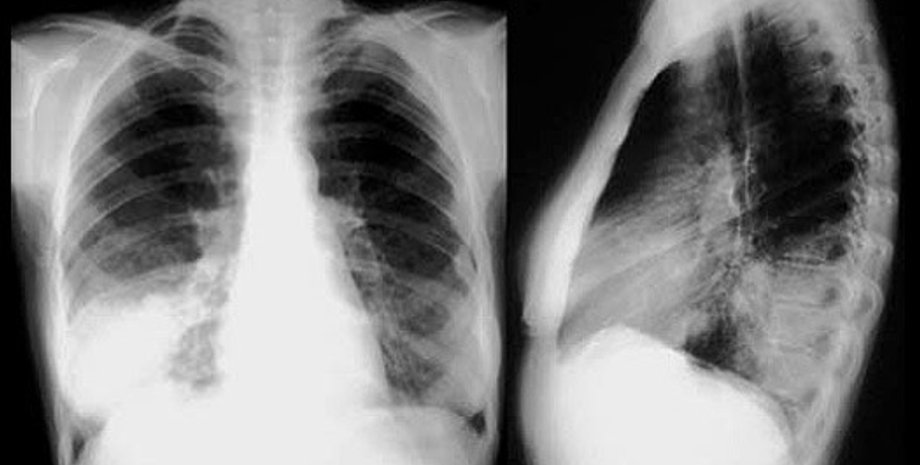

Как известно, человеческое легкое представляет собой сложное инженерное решение, созданное природой: площадь поверхности одного легкого у взрослого человека составляет около 70 квадратных метров, "упакованных" так, чтобы обеспечивать эффективный перенос кислорода и углекислого газа между кровью и воздухом. Однако ткань легкого трудно восстанавливать, и сейчас единственный способ заменить поврежденные участки органа - пересадка. Она сопряжена с высокими рисками отторжения органа и инфекции, поэтому через 10 лет после операции остаются в живых лишь 10-20% пациентов.